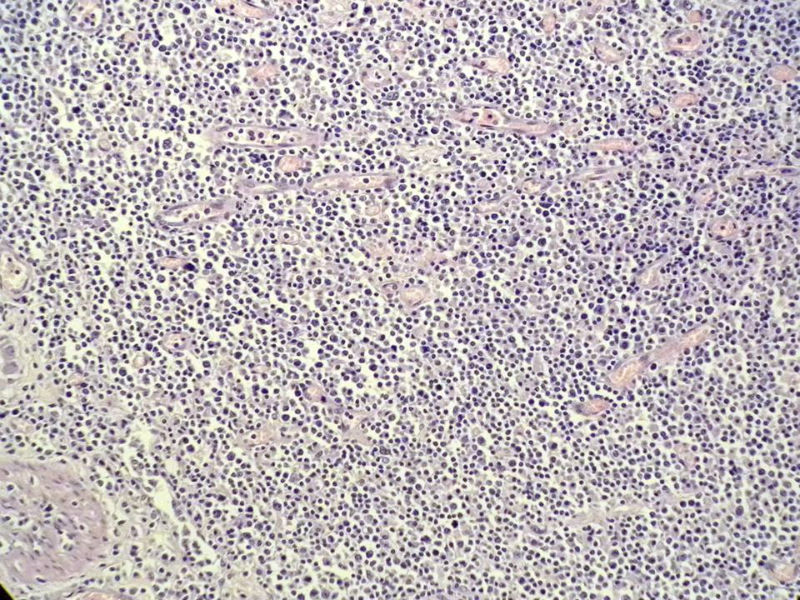

女,53岁,横结肠有9X6厘米大小溃疡,手术切除。

肉眼观仅是溃疡?有没有肠壁增厚、隆起?周围粘膜情况?肌层情况?有淋巴浆细胞样细胞、中心细胞,散在少量不成片的大细胞,不排除MALToma伴大细胞转化。

本例肉眼溃疡如溃疡性结肠炎,肠壁无明显增厚,表面辅以坏死,溃疡边缘稍隆起。镜下淋巴样细胞局限在粘膜层,肌层未见。谢谢!